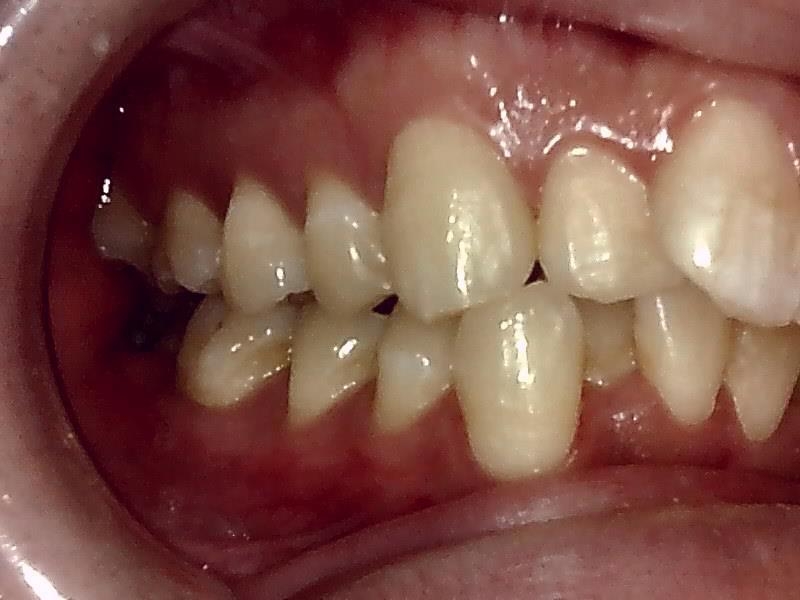

左側

右側 術前の写真